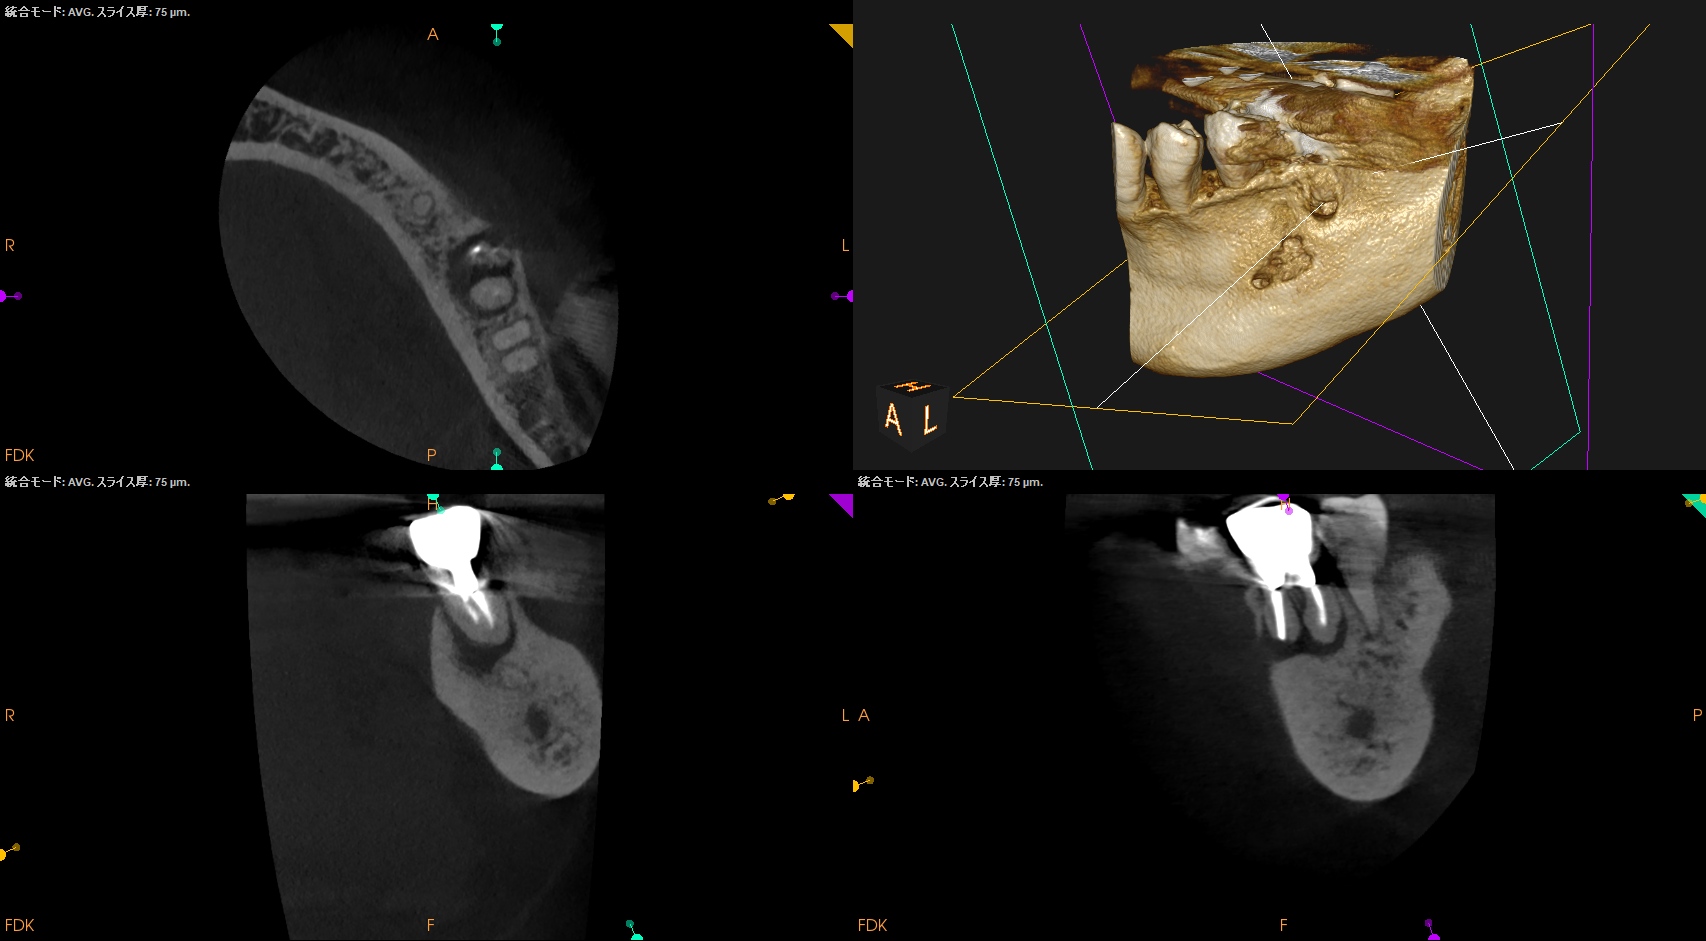

CBCT(2024.9.12)

MB

ML

D

治療はApicoectomyだ。

しかもM,Dともにである。